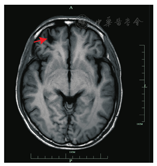

病例2,男,28岁,浙江仙居人,与病例1系朋友,因"反复发热、腹痛1月余,咳嗽3 d"于2019年7月17日与病例1一同入院。患者1个月前出现发热,体温约38℃,有腹痛,部位不固定,游动于上腹、下腹部,症状持续10 d不能缓解,于当地医院就诊,予头孢和青霉素抗感染治疗,体温正常,腹痛稍缓解,5 d前再次出现发热,体温达39.6℃,伴有多汗,曾有腹泻,无恶心、呕吐,3 d前出现咳嗽,稍感气急,无咳痰、咯血,为进一步治疗来我院就诊,门诊拟"发热待查"收治入院。体格检查:体温38.8℃,脉搏102次/min,呼吸20次/min,血压112/67 mmHg。神志清,精神可,皮肤巩膜无明显黄染,未见皮疹及皮下出血,浅表淋巴结未及,双肺呼吸音清,未闻及干湿啰音。心肺听诊未闻及病理性杂音。腹部平坦,上腹部压痛、无反跳痛。肝脾肋下未及,移动性浊音阴性。四肢肌力及张力正常,神经系统查体阴性。血常规示白细胞计数13.3×109/L,嗜酸性粒细胞占比0.454,嗜酸性粒细胞6.03×109/L,血红蛋白115 g/L,血小板344×109/L。超敏CRP 121.0 mg/L,ESR为4 mm/1 h。胸部CT示右肺及左肺下叶炎症,两肺数枚小结节,右侧气胸。头颅CT示两侧额叶软化灶(图2)。肝脏CT示肝脏肿大,肝内多发类圆形低强化区,多发炎性结节形成,盆腔积液。追问病史发现,与病例1曾于48 d前生食野生螃蟹,查血并殖吸虫抗体阳性。诊断:并殖吸虫病(腹型+肺型+脑型)。予吡喹酮片25 mg/kg,2次/d,口服3 d治疗后体温恢复正常,腹痛、咳嗽缓解出院。出院约1周后再次出现发热,继续使用吡喹酮治疗后3 d体温正常,于1个月后在当地医院复查血白细胞计数9.6×109/L,嗜酸性粒细胞占比0.349,嗜酸性粒细胞3.34×109/L,血红蛋白110 g/L,血小板计数369×109/L。肺部CT提示病灶较前吸收,气胸消失,双侧少量胸腔积液。2个月后再次复查,各指标均正常。

注:右侧额叶病灶(箭头示)